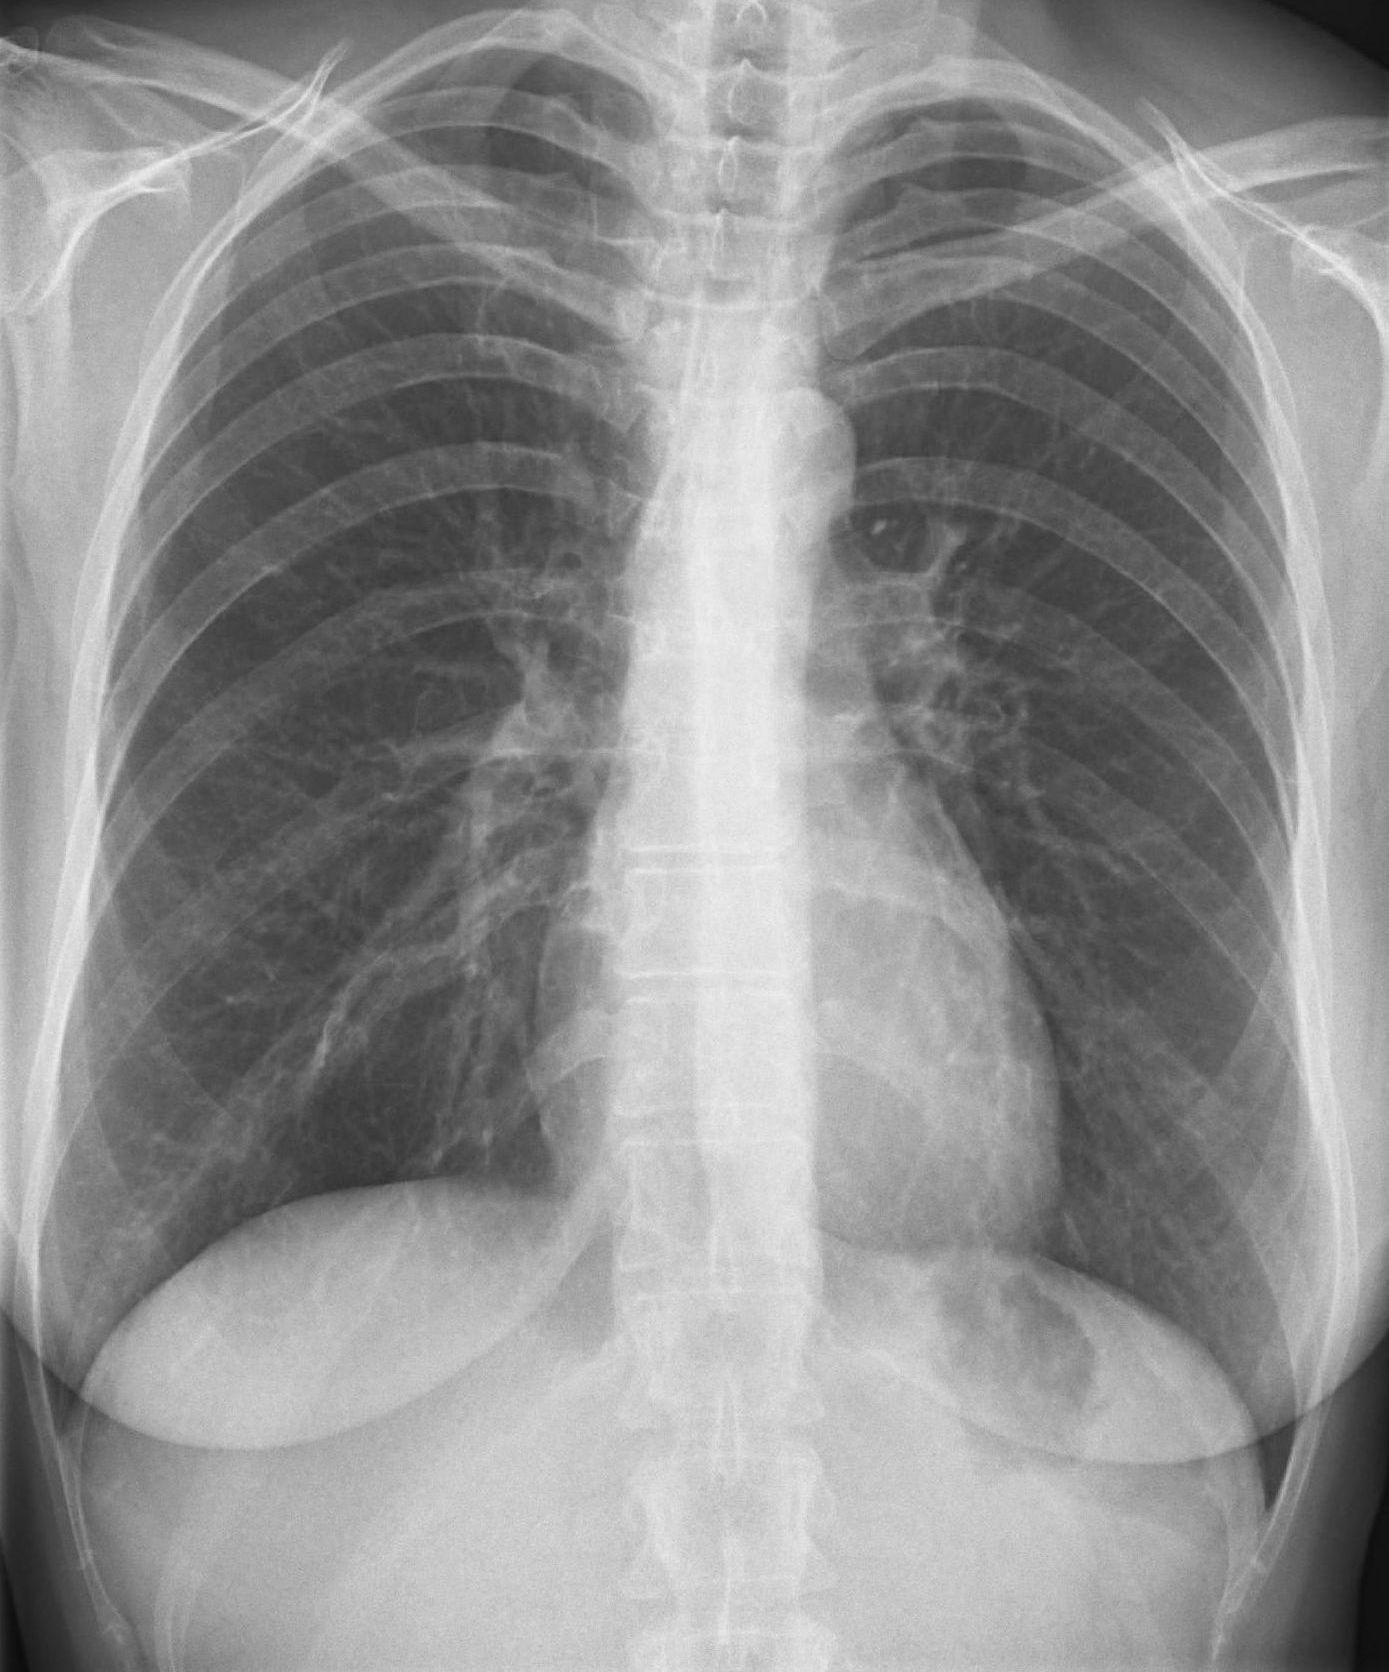

Röntgen der Lunge

Die Röntgenaufnahme der Lunge wird typischer Weise im Stehen am Wandstativ in zwei Ebenen in der Regel unter tiefer Einatmung durchgeführt. So können Veränderungen in der Lunge festgestellt und lokalisiert werden wie z.B. Tumoren, Lungenentzündung, Belüftungsprobleme von Lungenabschnitten und etliche andere Erkrankungen.